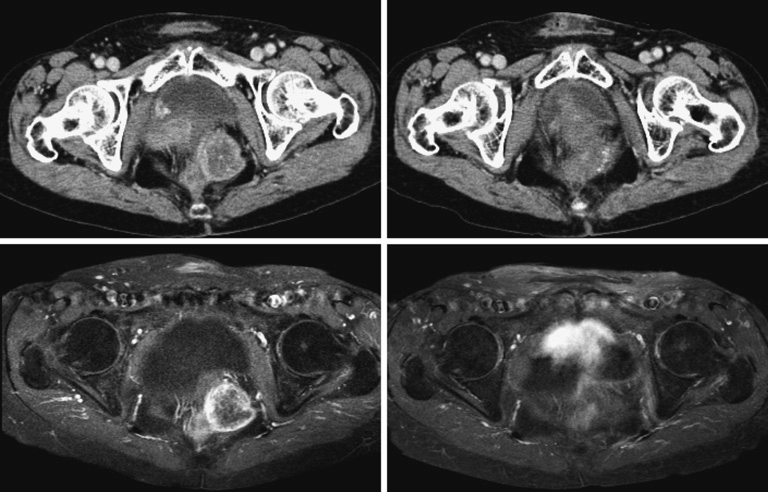

Như với UTTT nguyên phát, trong tình huống bệnh tái phát tại chỗ, xạ trị lại giúp cải thiện kết quả phẫu thuật ở hai thông số: Tỷ lệ đạt diện cắt R0 và tỷ lệ kiểm soát tại chỗ. Với những trường hợp tổn thương tái phát tại chỗ có khả năng cắt bỏ, không kèm theo nguy cơ diện cắt tiệm cận hay dương tính, chỉ định xạ trị lại có thể được bỏ qua. Tuy nhiên, đặc tính xâm lấn của tổn thương tái phát cũng như tình trạng xơ hóa sau phẫu thuật và xạ trị trước đó, việc đạt được diện cắt âm tính có thể là mộtthử thách thật sự. Liệu có hợp lí không khi mong đợi tế bào ung thư tái phát sau xạ trị vẫn nhạy cảm với tia xạ? Với các dữ liệu hiện có, dường như không có khác biệt rõ rệt về mức độ đáp ứng với xạ trị của UTTT nguyên phát và tái phát (Đã xạ trị trước đó). Valentini và cộng sự đã báo cáo tỷ lệ đáp ứng một phần là 36% và đáp ứng toàn bộ trên mô bệnh học (pCR) là 9% ở những bệnh nhân được phẫu thuật sau khi xạ trị lại8. Dijkstra và cộng sự báo cáo pCR của 9% bệnh nhân được xạ trị lại 30-30.6Gy (1.8-2Gy/fx) kết hợp hóa trị. Một nghiên cứu tại trung tâm MD Anderson cũng đã ghi nhận tỷ lệ pCR14% với chiến lược xạ trị tăng tốc, tăng số phân liều10, 11. Những kết quả này có thể so sánh với tỷ lệ pCR được báo cáo với hóa xạ trước mổ cho UTTT điều trị lần đầu, vào khoảng 7-20%12, 13. Dù còn thiếu những thử nghiệm tiến cứu so sánh phẫu thuật cứu vãn có hoặc không có xạ trị lại, dựa vào những dữ liệu trên, lợi ích của xạ trị bổ trợ trước mổ trong việc tăng cơ hội đạt được R0 và cải thiện kiểm soát tại chỗ có thể là một lý lẽ phù hợp để ngoại suy cho chỉ định xạ trị lại. Một dữ liệu hồi cứu lớn trên 565 bệnh nhân UTTT tái phát tại chỗ, 256 bệnh nhân trong đó trải qua hóa xạ tiền phẫu, ghinhận phẫu thuật đạt được R0 cho 43% BN nhận xạ trị lại, so với 26% ở nhóm không xạ trị tiền phẫu. Một phân tích gộp đánh giá xạ trị lại cho UTTT tái phát tại chỗ, so sánh xạ trị lại tiền phẫu, hoá xạ tiền phẫu và hóa xạ bổ trợ cho thấy tỷ lệ đạt R0 và kiểm soát bệnh tại chỗ cao nhất ở nhóm hóa-xạ trị lại tiền phẫu14.

Xạ trị trong mổ (IORT) đã được ứng dụng trong điều trị cứu vãn cho các bệnh nhân UTTT tái phát tại chỗ, với phần lớn dữ liệu bằng chứng ủng hộ IORT kết hợp cùng xạ trị trước mổ21. IORT tăng cường một liều xạ lớn đến khối u/giường phẫu thuật trong khi các cơ quan nguy cấp (OARs) an toàn ngoài phạm vi tác động. IORT sử dụng electron (IOERT) hoặc kỹ thuật áp sát suất liều cao (HDR-IORT). Một báo cáo từ Mayo Clinic trên 248 bệnh nhân với tái phát trong trường chiếu, được điều trị cứu vãn sử dụng hoá – xạ trị lại trước mổ và IOERT. Trung vị của liều xạ ngoài là 27,5 Gy (5 – 39,5 Gy). IOERT đóng góp mức liều dao động từ 12,5 – 20 Gy tuỳ theo trạng thái diện cắt. Tỷ lệ tái phát tại chỗ và OS 5 năm tương ứng lần lượt là 37% và 46%6. Diện cắt phẫu thuật có liên quan đến kết quả kiểm soát bệnh tại chỗ khi tỷ lệ tái phát tại chỗ 5 năm với diện cắt R0, R1/R2 tương ứng lần lượt là 21% và 32%. Dữ liệu từ Hà Lan trên 135 bệnh nhân UTTT tái phát tại chỗ, được hoá – xạ trị lại mức liều 30 – 30,6 Gy, sau đó phẫu thuật và IOERT (10 – 15 Gy), so sánh với nhóm bệnh nhân UTTT tái phát tại chỗ chưa xạ trị trước đó, được hoá xạ trị trước mổ đủ liều (~ 50 Gy) và phẫu thuật cùng với IOERT, nhóm thứ 3 là các bệnh nhân UTTT tái phát tại chỗ chưa xạ trị trước đó nhưng được điều trị cứu vãn bằng phẫu thuật và IOERT4. 55% bệnh nhân hoá – xạ trị lại đạt được phẫu thuật R0 so với 63% và 42 % tương ứng lần lượt ở nhóm nhận hoá xạ trị trước mổ đủ liều và không xạ trị trước mổ. Tỷ lệ sống thêm không tái phát tại chỗ 5 năm là 45,9%, 58,7%, 35% tương ứng lần lượt ở nhóm hoá – xạ trị lại trước mổ, hoá xạ trị trước mổ đủ liều và không xạ trị trước mổ. Hyngstrom cùng cộng sự báo cáo kết quả của 70 bệnh nhân UTTT tái phát tại chỗ, được điều trị cứu vãn với xạ trị lại trước mổ (Có/không kết hợp hoá trị) đến 39 Gy (1,5 Gy BID), theo sau bởi HDR-IORT (10-15 Gy)22. Tỷ lệ kiểm soát tại chỗ 5 năm là 56%, không có sự khác biệt giữa nhóm được phẫu thuật R0 và R1. Kết quả này gợi mở rằng IORT có thể giúp giảm thiểu nguy cơ tái phát tại chỗ cho những trường hợp diện cắt dương tính.